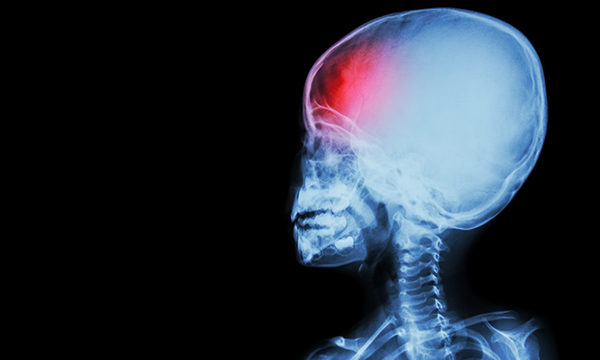

Updated guidelines on how to recognise the signs of a stroke in a child have been published by the Royal College of Paediatrics and Child Health (RCPCH) and the Stroke Association.

Stroke